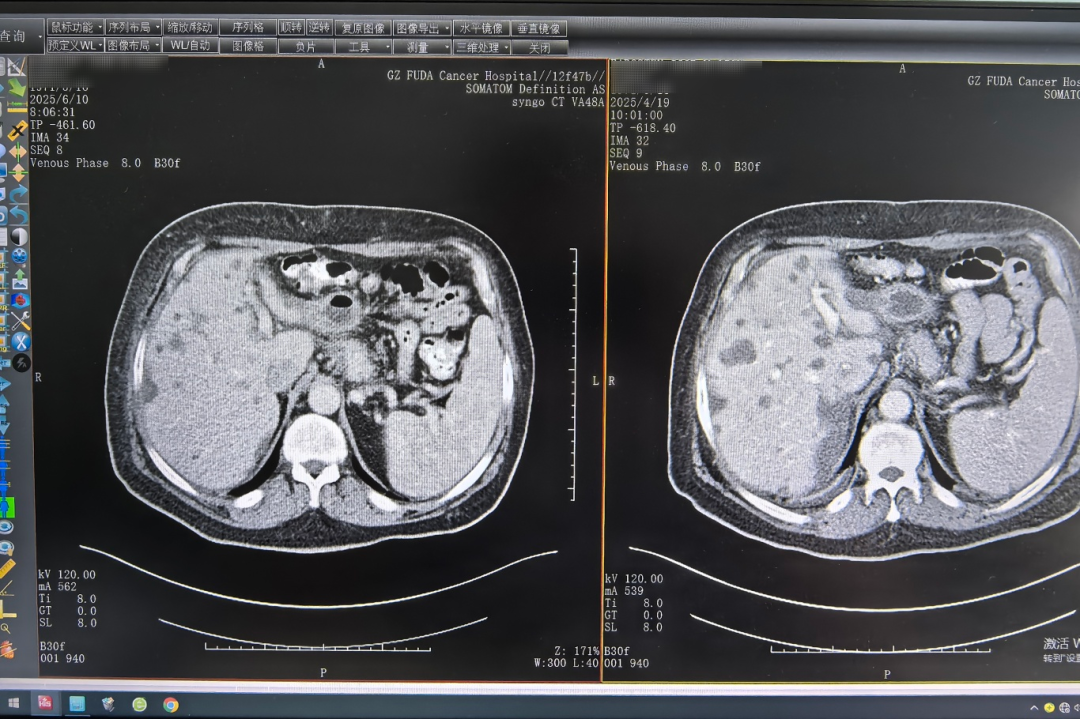

在首次接受免疫和靶向治療后,伊戈?duì)柛械剿母瓮吹玫搅孙@著緩解。兩三個(gè)療程后CT影像提示:胰腺病灶、肝臟多發(fā)轉(zhuǎn)移瘤較前縮小。醫(yī)療四科團(tuán)隊(duì)立馬根據(jù)其身體狀況,及時(shí)調(diào)整治療方案,為其施行肝臟腫瘤冷凍消融術(shù),即在影像設(shè)備的引導(dǎo)下,經(jīng)皮把消融針直接穿到肝臟腫瘤內(nèi),通過快速冷凍和復(fù)溫循環(huán),精準(zhǔn)滅活腫瘤細(xì)胞。

△左圖為6月10日影像結(jié)果,右圖為4月19日影像結(jié)果